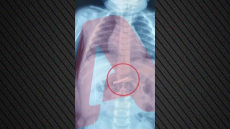

Δράμα: Αεροδιακομιδή δίχρονου αγοριού στο Παίδων λόγω σοβαρής λοίμωξης του αναπνευστικού

Το παιδί μεταφέρθηκε με ασθενοφόρο του ΕΚΑΒ από τη Δράμα στο αεροδρόμιο «Μέγας Αλέξανδρος» της Καβάλας και εν συνεχεία, με απόλυτη ασφάλεια, στο νοσοκομείο της Αθήνας όπου και νοσηλεύεται